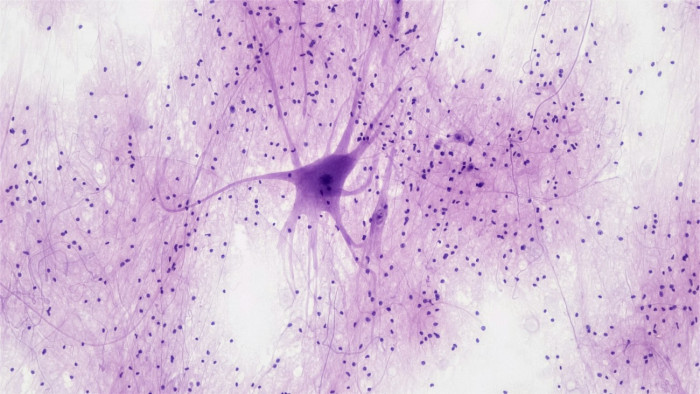

Újabb lépés az Alzheimer-kór kezeléséhez

Az emberi agyban ugyanazok a sejtek, mechanizmusok végzik a térbeli navigációt, mint amelyekkel a gondolataink között barangolunk - mondta Buzsáki György, a New York-i Egyetem Brain-prize-díjas professzora a CEU idegtudományi szimpóziumán az InfoRádiónak.